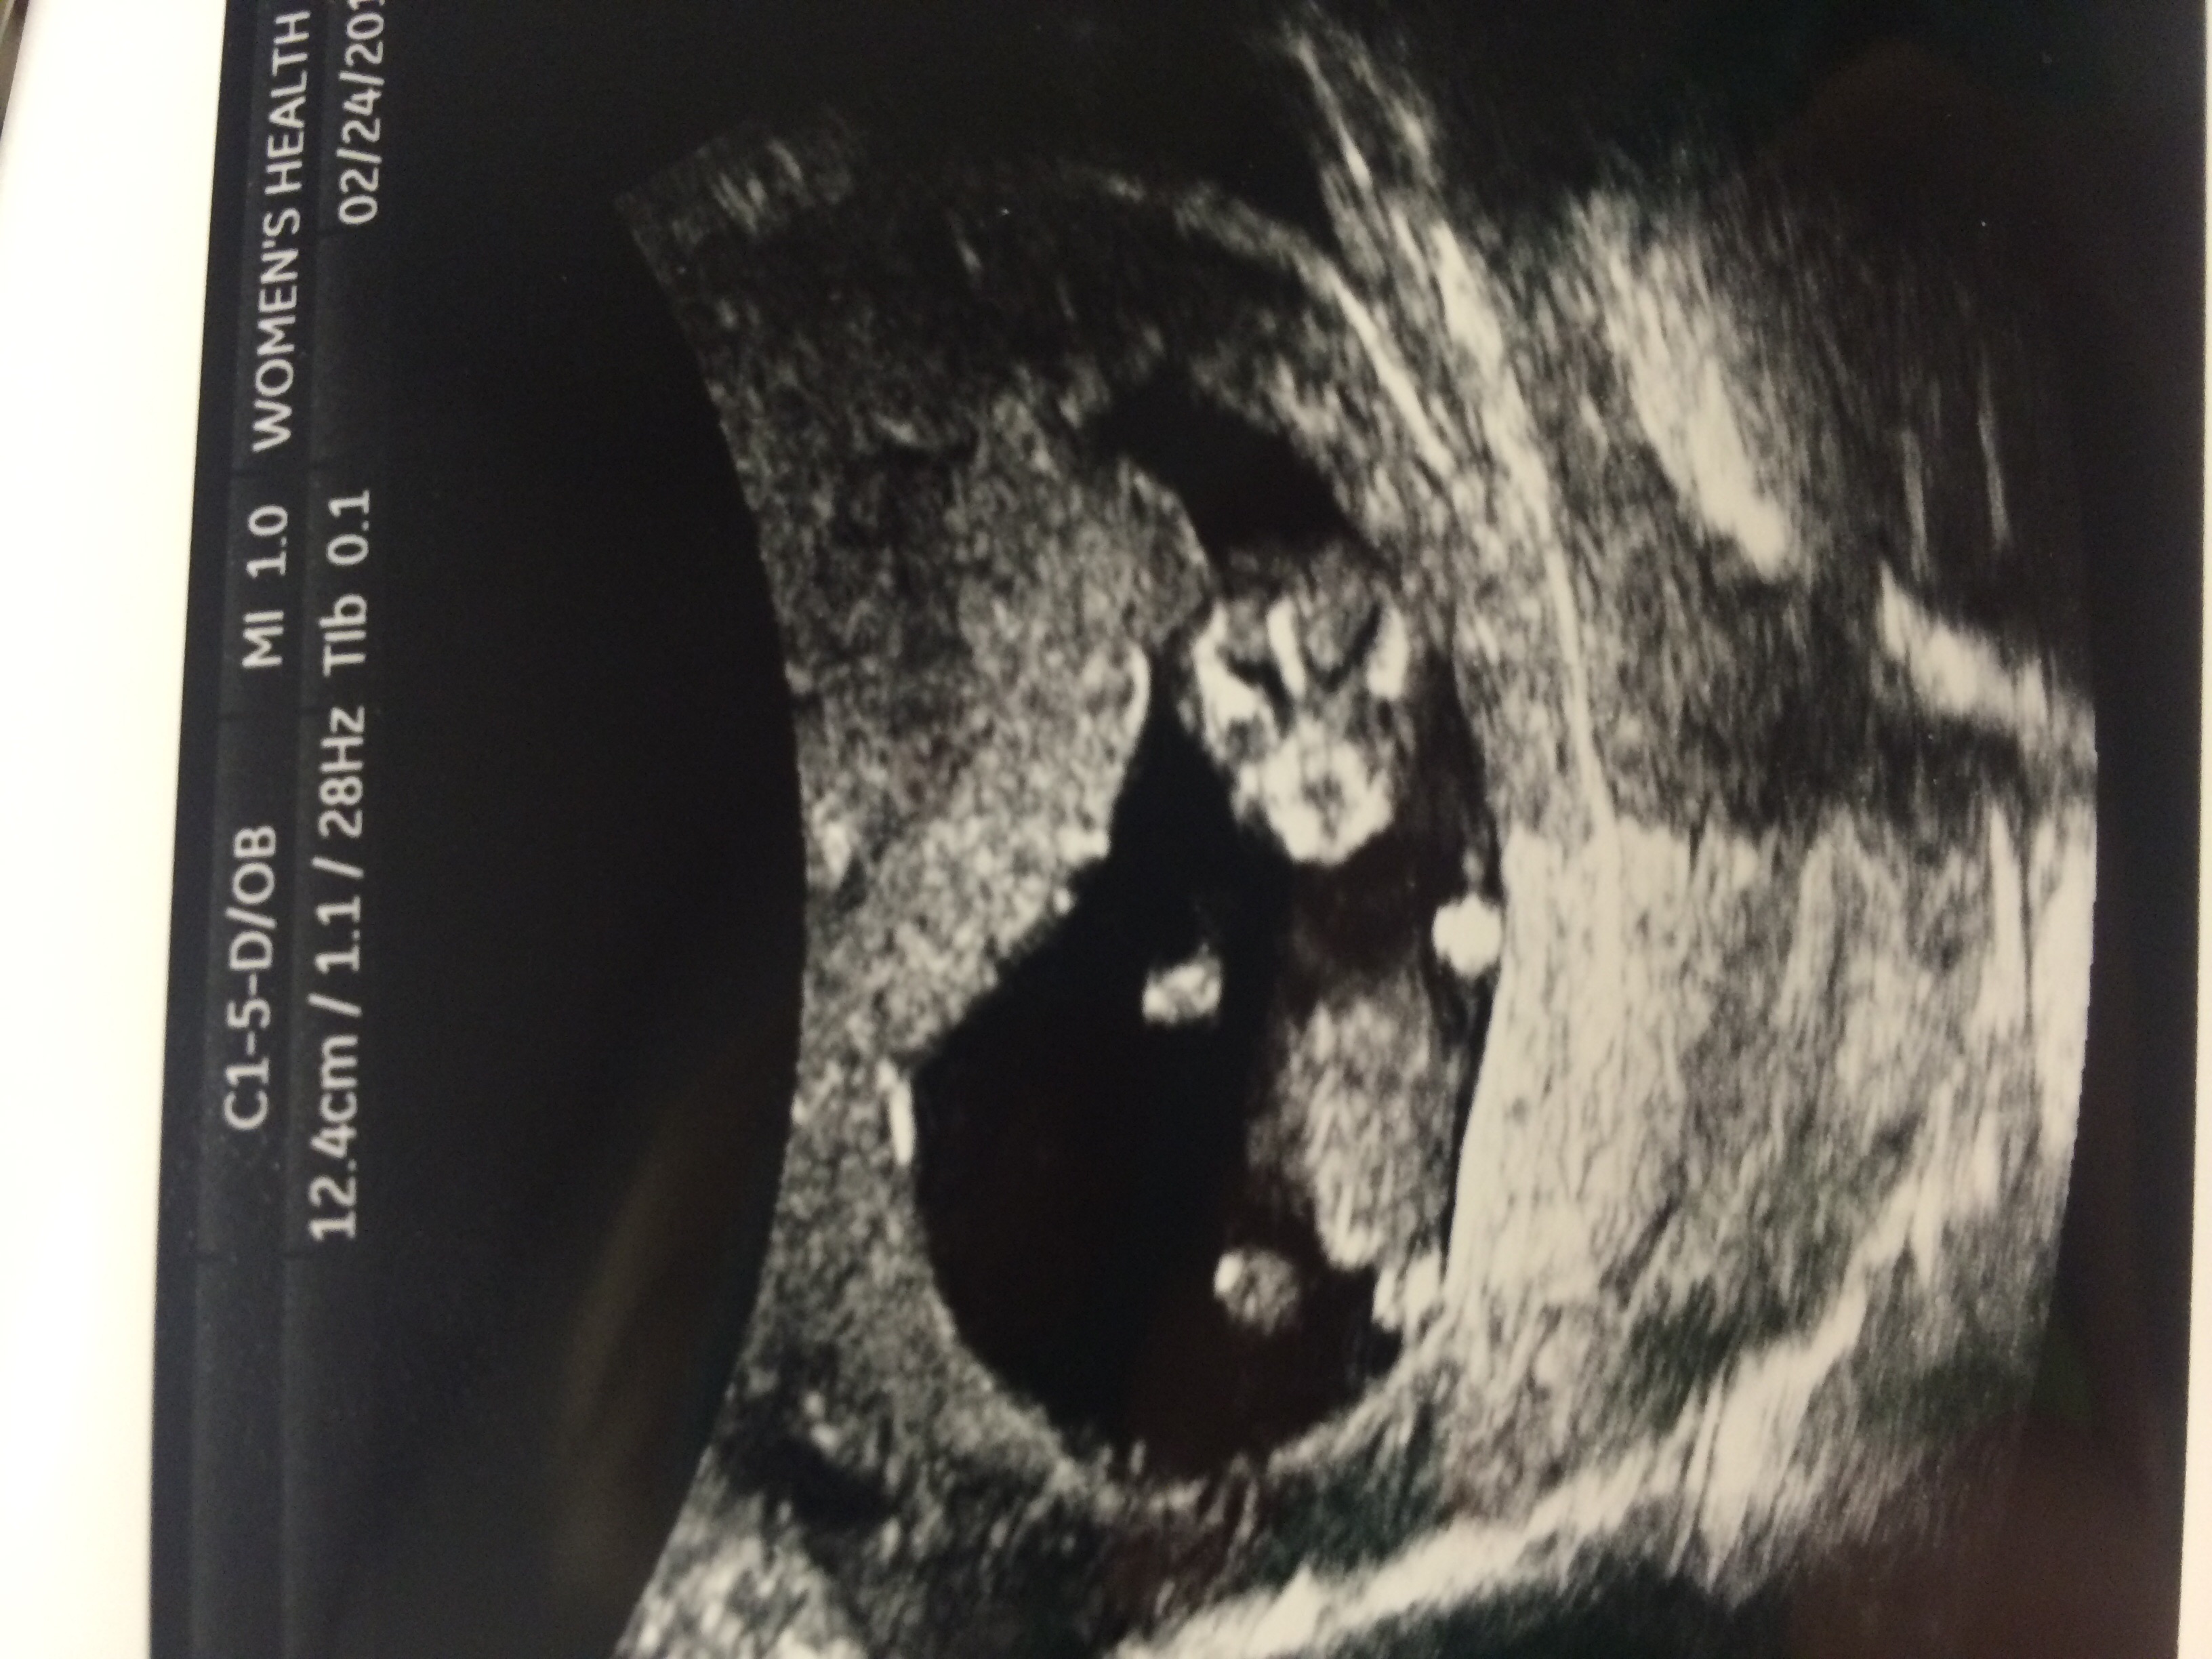

Quick scan done at 11weeks 3 days. FTM. Can't believe how big our baby has gotten from my 7week scan! (There were some concerns so I have gotten a couple of scans)